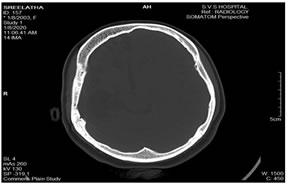

A 17-year-old female child was brought for deteriorated mental status and a history of few episodes of left focal seizures with secondary generalization since 2½ years. There was no history of head trauma. The seizure episodes were followed by decreased movement of the left side of the body and occasionally drooling of saliva from the left side. Perinatal vs. birth history was uneventful. The patient did not attend school. On examination, the child was undernourished with very poor cognitive function. Vitals were normal. Positive clinical findings noted were – microcephaly, severe mental retardation with an intelligence quotient of 40 and left-sided facial palsy. Examination of the central nervous system revealed left hemiparesis. Examination of other systems was unremarkable. Radiographs of skull showed thickening of the right hemicalvarium [Figure 1]. Non-contrast computed tomography and magnetic resonance imaging (MRI) reveled unilateral atrophy of the right cerebral hemisphere and ex- vacuo dilatation of ipsilateral lateral ventricle with prominence of sulci [Figures 2 and 3]. Thickening of the right hemicalvarium was noted measuring 7-8 mm compared to 5 mm on the left side (in frontal region at level of lateral ventricles) and enlarged right frontal sinus. These findings were suggestive of DDMS.

Figure 1: Skull radiographs: Anterioposterior and lateral views showing thickening of the right hemicalvarium (asterisk *); Figure 2: Axial sections of non-contrast magnetic resonance imaging (T1) and computed tomography (brain window) of the brain showing diffuse atrophy of the right cerebral hemisphere with ex-vacuo dilatation of the right lateral ventricle and prominence of sulci over the right cerebral hemisphere. Compensatory thickening of the right hemicalvarium is also seen; Figure 3: Coronal (T2) Magnetic resonance imaging and axial computed tomography(bone window) of the brain showing diffuse atrophy of the right cerebral hemisphere with ex-vacuo dilatation of the right lateral ventricle and compensatory thickening of the right hemicalvarium